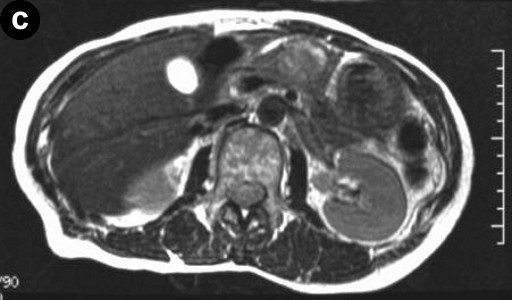

A 66-year-old Japanese woman was admitted to our hospital with a pancreatic tumor indicated in medical examinations. There was no remarkable past history of disease. No inherited factors or marked diseases in her family were noted. On admission, she had no complaints, and physical examinations and laboratory data revealed no noticeable abnormalities. Serum levels of CA 19-9 and s-pancreas-1 (pancreatic associated) antigen were within the normal range. Magnetic resonance imaging (MRI) revealed a mass, 3 cm in diameter, in the body of the pancreas, showing hypointensity on T1-weighted images, marked enhancement after gadolinium diethylenetriaminepenta acetic acid (Gd-DTPA) administration, and mixed hypo- and hyperintense patterns on T2-weighted images (Figure 1abc). Magnetic resonance cholangiopancreatography (MRCP) and endoscopic retrograde cholangiopancreatography (ERCP) showed no abnormal findings. The results of bacterial cultures of the pancreas juice were negative. Computed tomography (CT) revealed a 3 cm solid and cystic tumor within the body of the pancreas, with high resorption CT levels of the cystic components (Figure 1d). Contrast-enhanced CT showed partial enhancement of the solid components, and the main pancreatic duct was not involved in the tumor. Ultrasonography (US) and endoscopic ultrasonography (EUS) revealed a 3 cm solid and cystic tumor with low echoic margins in the body of the pancreas (Figure 2a). Contrast-enhanced US with Levovist® (Bayer Schering, Berlin, Germany) showed partial enhancement of the solid components (Figure 2b). Angiography showed no abnormal findings. From these imaging findings, mucinous cystic neoplasms or acinar cell tumors were considered.

Figure 2. a. US reveals a solid and cystic tumor with low echoic margin in the body of the pancreas. b. Contrast-enhanced US with Levovist® (Bayer Schering, Berlin, Germany) shows partial enhancement at the solid component. |

The solid and cystic pattern observed on CT was also seen with US, in which hypoechoic and/or cystic findings were noted in a high percentage of cases. However, the details of the solid components were revealed more clearly by US as compared to CT or MRI. Moreover, in the present case, contrast-enhanced US with Levovist® (Bayer Schering, Berlin, Germany) showed partial enhancement at the solid component.